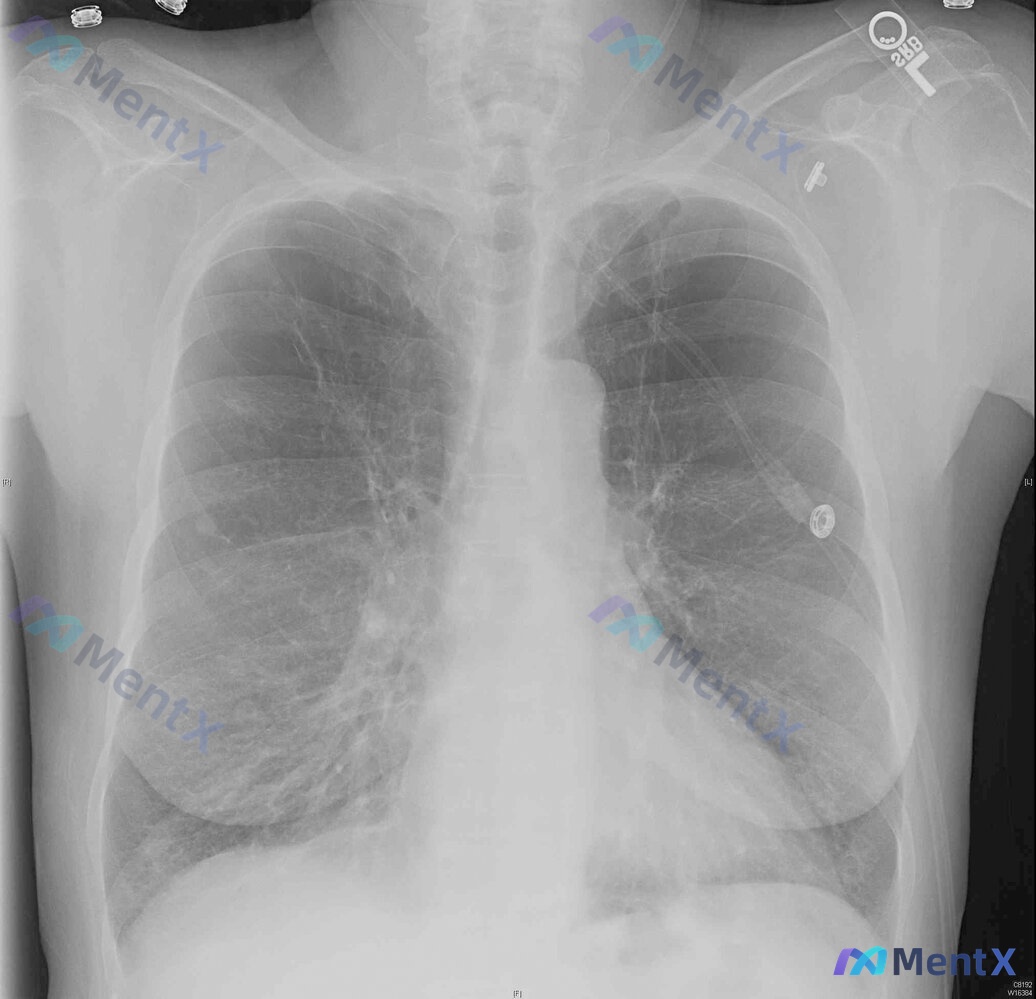

整理到一个挺有警示意义的病例: 85岁女性,长期居住在固定护理机构,因12小时呼吸困难被救护车送急诊。 初始生命体征与一般情况: - 心率140次/分,呼吸29次/分 - 未吸氧时SpO2 72%,予100%氧气(非重复呼吸面罩)后纠正为86% - 难以唤醒,有短暂的胸膜刺激性发作 - 无预先指示,...